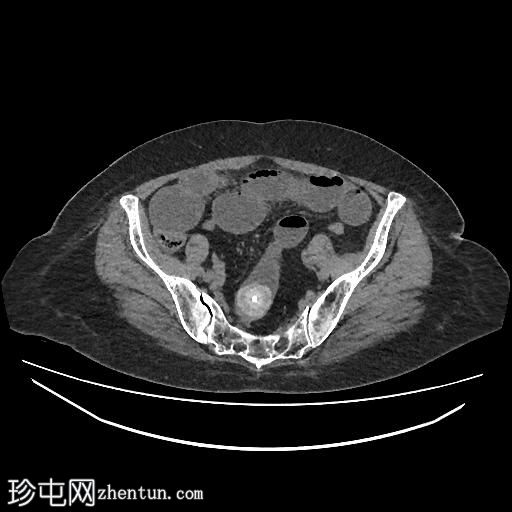

轴位

平扫

胆囊缩小,囊壁增厚,提示慢性炎症改变。胆囊(底部)与十二指肠(球部)腔之间可见细小瘘管,胆囊内及肝内、肝外胆管内均可见气体(胆道积气)。

远端空肠内嵌顿一枚较大的胆结石(3.5 cm),近端空肠袢扩张,回肠袢、末端回肠及结肠均塌陷。